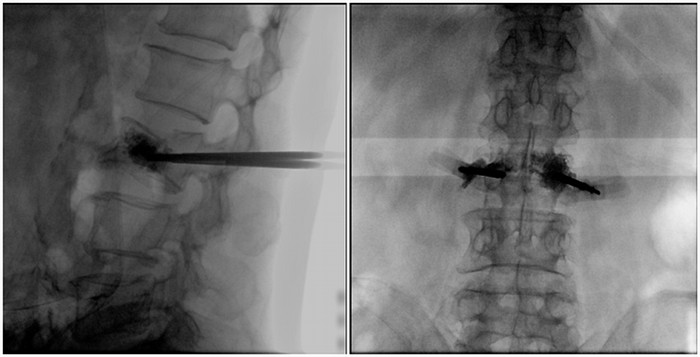

術中切口5毫米,在大平板C臂機的透視指引下,確定了進針的方向及進針的深度。經(jīng)椎弓根向椎體置管,建立通道,插入骨擴張器(球囊)。球囊擴張恢復椎體高度,并在椎體內形成空腔,確定骨水泥的注入劑量,并注入骨水泥觀察其擴散情況。

大平板C臂機臨床圖像